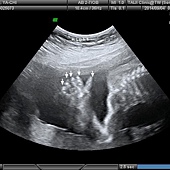

脊椎骨和小屁屁......寶寶翻身啊!

(上圖)上面一排的脊椎,右邊較亮白白的弧線是阿柴的小屁屁。趴著有這舒服嗎?